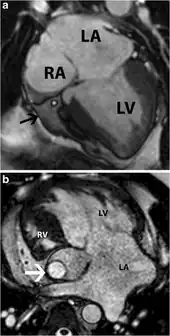

Tricuspid atresia is a form of congenital heart disease whereby there is a complete absence of the tricuspid valve.[2] Therefore, there is an absence of right atrioventricular connection.[2] This leads to a hypoplastic (undersized) or absent right ventricle. This defect is contracted during prenatal development, when the heart does not finish developing. It causes the systemic circulation to be filled with relatively deoxygenated blood. Because of this, hypoxia occurs, so other defects must occur to maintain blood flow. Because of the lack of an atrioventricular connection, an atrial septal defect (ASD) must be present to fill the left atrium and the left ventricle with blood.[3] Since there is a lack of a right ventricle, there must be a way to pump blood into the pulmonary arteries, and this is accomplished by a ventricular septal defect (VSD). The causes of tricupsid atresia are unknown.[4]

A combined atrial septal defect (ASD) and a ventricular septal defect (VSD) can be present to maintain blood flow-from the right atrium, the blood must flow through the ASD to the left atrium to the left ventricle and through the VSD to the right ventricle to allow access to the lungs.